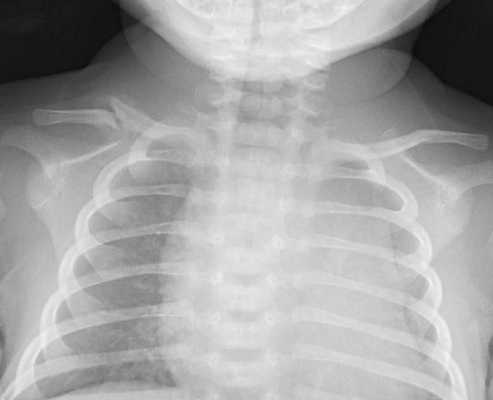

При парезе диафрагмы у новорожденного развивается одышка, парадоксальное дыхание, цианоз, выбухание грудной клети на пораженной стороне. Выявлению пареза способствует рентгеноскопия и рентгенография грудной клетки, при которых определяется высокое стояние и малоподвижность купола диафрагмы. На этом фоне у детей может развиться застойная пневмония. Лечение родовой травмы заключается в чрескожной стимуляции диафрагмального нерва; при необходимости – ИВЛ до восстановления адекватного самостоятельного дыхания.